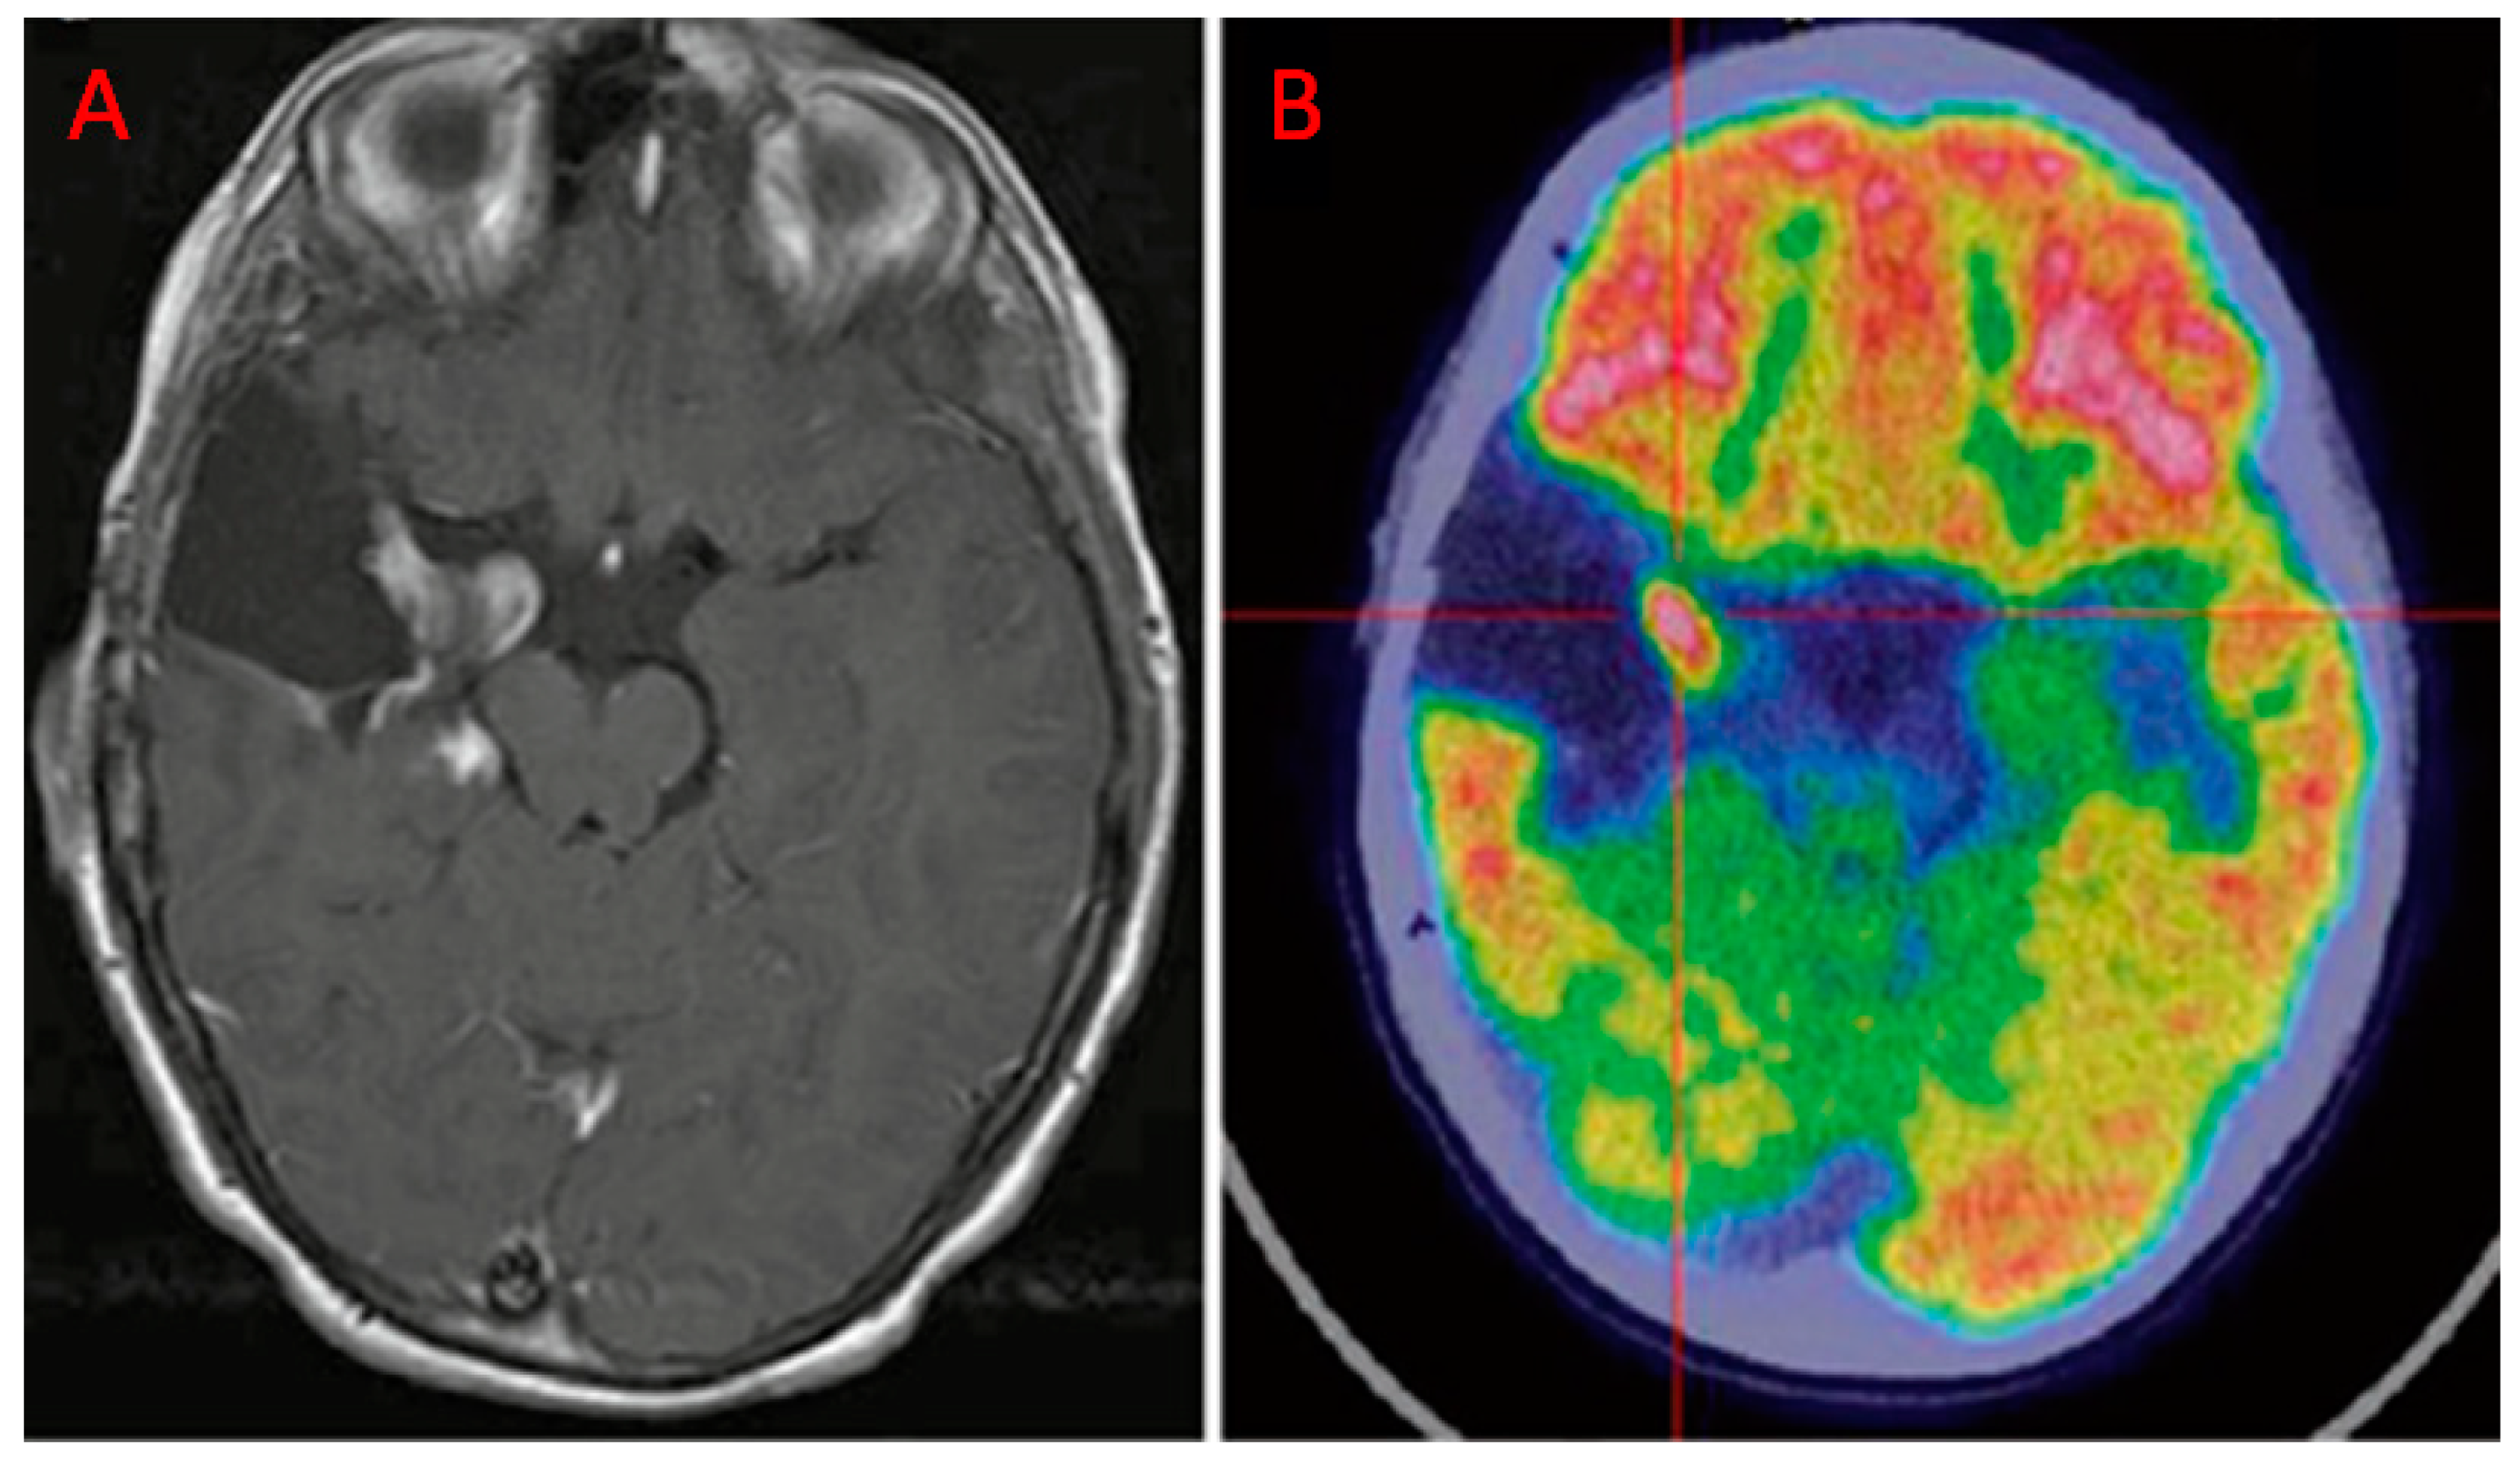

- Valentini, M.C.; Mellai, M.; Annovazzi, L.; Melcarne, A.; Denysenko, T.; Cassoni, P.; Casalone, C.; Maurella, C.; Grifoni, S.; Fania, P.; et al. Comparison among conventional and advanced MRI, (18)f-fdg PET/CT, phenotype and genotype in glioblastoma. Oncotarget 2017, 8, 91636–91653. [Google Scholar] [CrossRef]

| Valentini et al. [20] | 2017 | R | 12 (48 biopsy specimens) | GBM | PET/CT | DWI, DTI, DSC-PWI, MRSI | Highest values of rCBV, Cho/Cr, Cho/NAA, proportional decrease of SUVmax with increasing distance from the CE region. At histological examination, the CE region showed maximum tumor histological malignancy and presented the maximum values of rCBV, Cho/Cr, Cho/NAA, LL and SUVmax. |